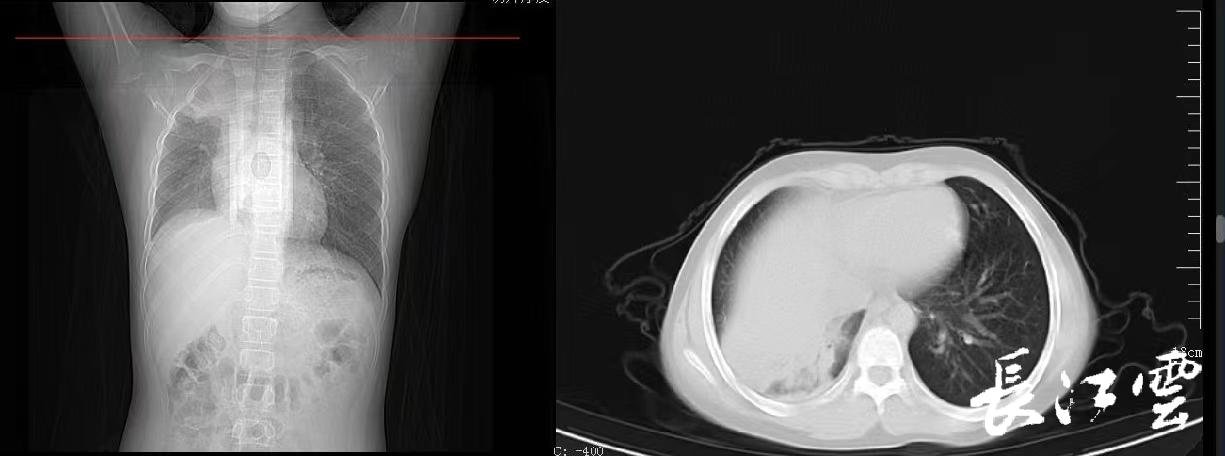

12岁的舟舟一周前出现阵发性咳嗽并伴有发热,家长害怕去医院会交叉感染,于是在家自行吃药治疗。退热之后,舟舟咳嗽的症状没有好转,甚至开始咳后呕吐,活动后出现胸闷的情况,家长这才将舟舟送往湖北省中医院(湖北中医药大学附属医院)儿科就诊。接诊的儿科主任张雪荣经过一系列的查体后初步判断舟舟已经发展成肺炎了,“收治入院后查胸片显示,孩子右肺内带见片状软组织样高密度影,右肺野内亦可见片状高密度影,右侧肋膈角变浅变钝,膈面模糊。考虑右肺部分不张伴胸腔积液可能。”看到胸片上舟舟的一侧肺部组织大面积变白后,家长既自责又后悔。好在经中西医结合治疗后,舟舟目前的症状已经明显好转。